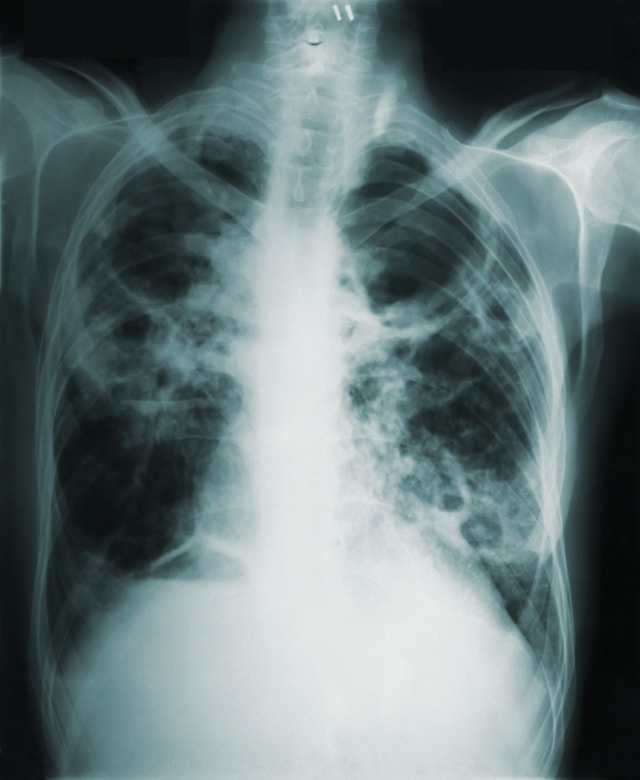

TB isn’t a newbie on the health scene. It’s been around for centuries, causing havoc long before Instagram influencers and TikTok trends. This infectious disease is caused by a bacterium called Mycobacterium tuberculosis. It primarily affects the lungs but can also target other parts of the body like the kidneys, spine, and brain. It spreads through the air when an infected person coughs or sneezes, making it highly contagious.